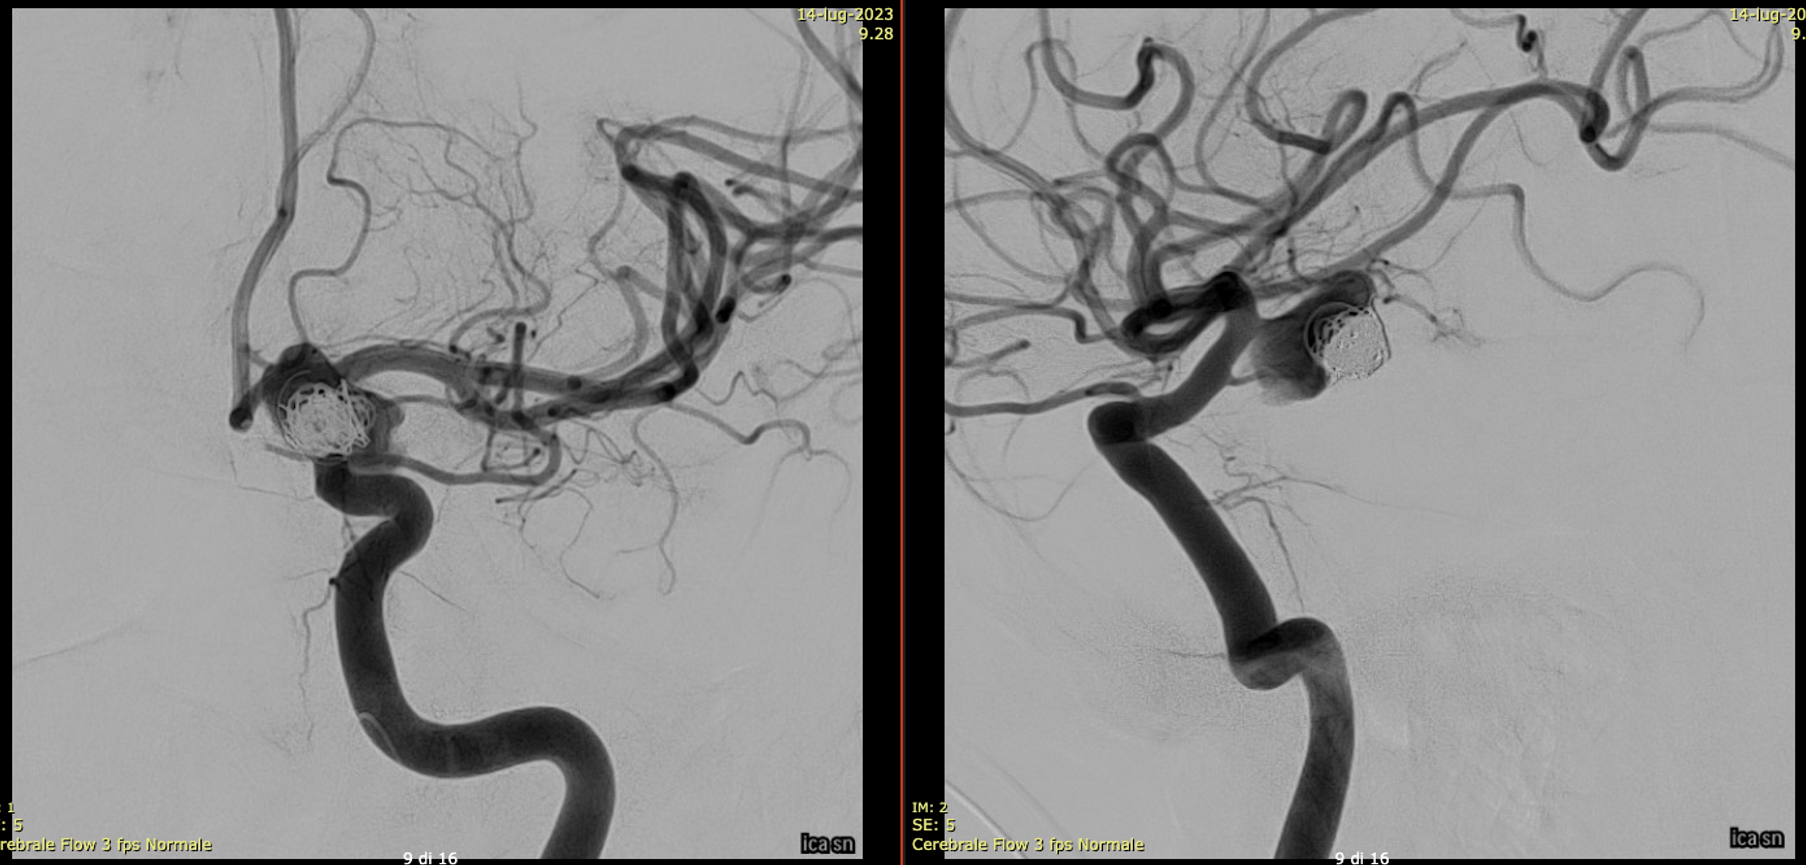

Important Case of Aggressive Anterior Choroidal Aneurysm

A young man with an unruptured but symptomatic dissecting aneurysm at the origin of the Anterior Choroidal artery. Treated in acute phase with coils; in the meantime the aneurysm has grown.

A Silk Vista was implanted a couple of weeks after coiling

Immediately after the release of the SV, we saw a minimum movement of the distal end to fishmouthing

A Credo stent was used to keep the SV apposed to the vessel wall

One month later the aneurysm was still growing — as they frequently do.

A Bentley Coronary Stent 3 x 8 mm was implanted, progressively inflated (even with a 3.5 PTA balloon) until no more contrast entered the aneurysm. The USA version of Bentley is the Papyrus — Bentley is better.

Noncontrast / dry Vaso-CT, 22 cm FOV 20 seconds acquisition, followed by a secondary reconstruction with 50% FOV and 5123 resolution; Thick MIP.

We can clearly see the three stents. The Credo seems too rigid and probably is not fully open in the curve. The Bentley (arrows) is a little bit overinflated (consider that at this level the coils reduce the image quality). SV is open with some irregularity.

This is the problem with using laser-cut stents for fishmouthing. Alternative is a relatively low coverage braided stent like Evo or LVIS Jr.